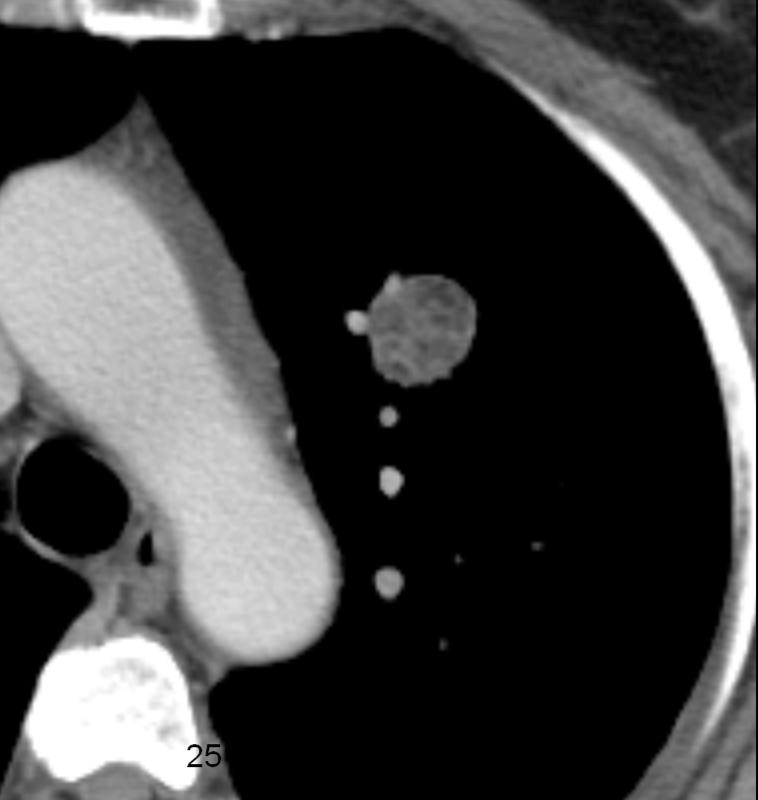

Gallery Congenital Hamartoma

Hamartoma